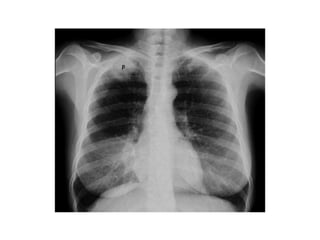

El término Cancer de pulmon se utiliza

para los tumores que surgen en el

epitelio respiratorio

(Bronquios,Bronquiolos y Arveolos)

.